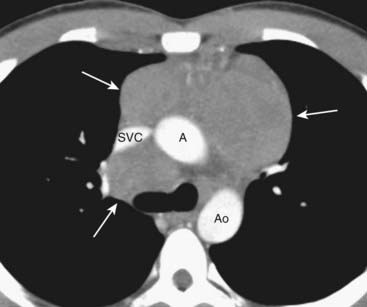

Figure 12-5 CT of anterior mediastinal adenopathy in Hodgkin disease.

On CT, lymphomas will produce multiple, lobulated soft-tissue masses or a large soft-tissue mass from lymph node aggregation (solid white arrows). The mass is usually homogeneous in density, as in this case, but may be heterogeneous when the nodes achieve a sufficient size to undergo necrosis (areas of low attenuation, i.e., blacker) or hemorrhage (areas of high attenuation, i.e., whiter). The superior vena cava (SVC) is compressed by the nodes while the ascending (A) and descending aorta (Ao) are typically less so.

image Lymphoma will produce multiple, lobulated soft-tissue masses or one large soft-tissue mass from lymph node aggregation.

image The mass is usually homogeneous in density on CT but may be heterogeneous when it achieves a sufficient size to undergo necrosis (areas of lower attenuation, i.e., blacker) or hemorrhage (areas of higher attenuation, i.e., whiter) (Fig. 12-5).